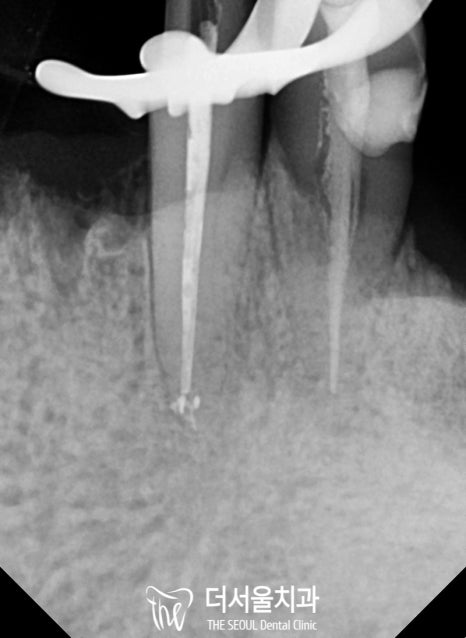

하악 신경치료를 진행한 다음,

오염된 치수를 제거하고 근관의 길이를 측정했습니다.

구치부

이후 소독 과정을 거친 뒤,

뿌리 끝부분부터 빈 공간이 남아있지 않도록

밀봉을 도와드렸습니다.

자, 여기서 Point!

뿌리 끝까지 확실하게 밀봉하는 것이 중요합니다.

이 과정의 결과를 좌우할 수 있는 관건이 되는데요.

만약 뿌리 끝까지 채워지지 않았다?

그러면 또 다른 염증이 생기거나,

같은 곳에 병소가 재발하는 일이 생기게 되죠.

전치부 / 구치부

숨어있는 미세 근관까지 빼곡하게 채워주었습니다.

파노라마 사진을 보면 뿌리 끝까지 채워진 모습을 볼 수 있네요.